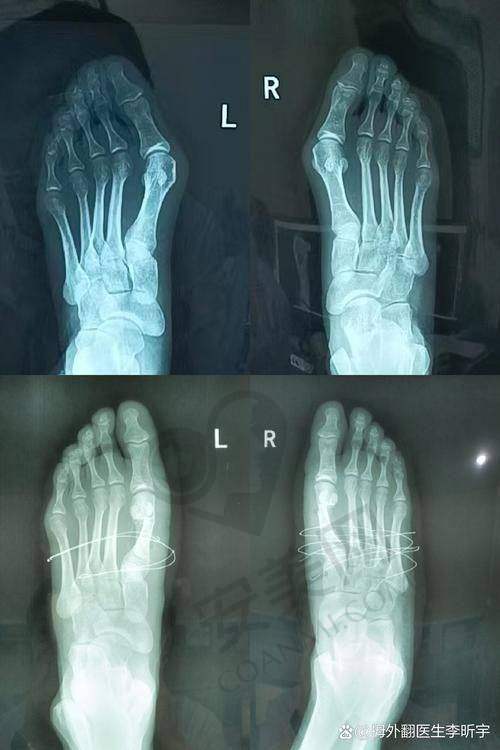

苏敬达医生告诉我,他采用的是一种独特的治疗技术,这种技术和传统的治疗方法有较大的不同。传统的拇外翻治疗方法可能会有创伤大、修复慢等问题,而他的技术可以做到微创治疗,切口小,修复快,而且术后成效非常好。他还向我展示了特别多成功的实例,看着那些患者术后修复得那么好,我心里充满了希望。

通过这次就诊经历,我深刻地体会到了北京圣嘉新苏敬达拇外翻技术的特色。首先,就是微创治疗。这种技术切口小,对脚部的损伤非常小,术后修复快,大大减少了患者的痛苦。其次,苏敬达医生的技术非常不错,他在手术过程中操作精细,能够正确地矫正拇外翻问题,确保了治疗成效。